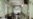

"Даже ночью около больниц, где делают компьютерную томографию, собирается просто огромная очередь из "скорых", по 20-30 машин. Соответственно, все эти "скорые" выключаются из оборота, – рассказывает медик. – У тебя вполне может быть пневмония с каким-то сравнительно небольшим процентом поражения [легких] – хотя любой процент сейчас важен, потому что он мгновенно перерастает в намного больший. Процентов до 50 – могут просто не положить в больницу".